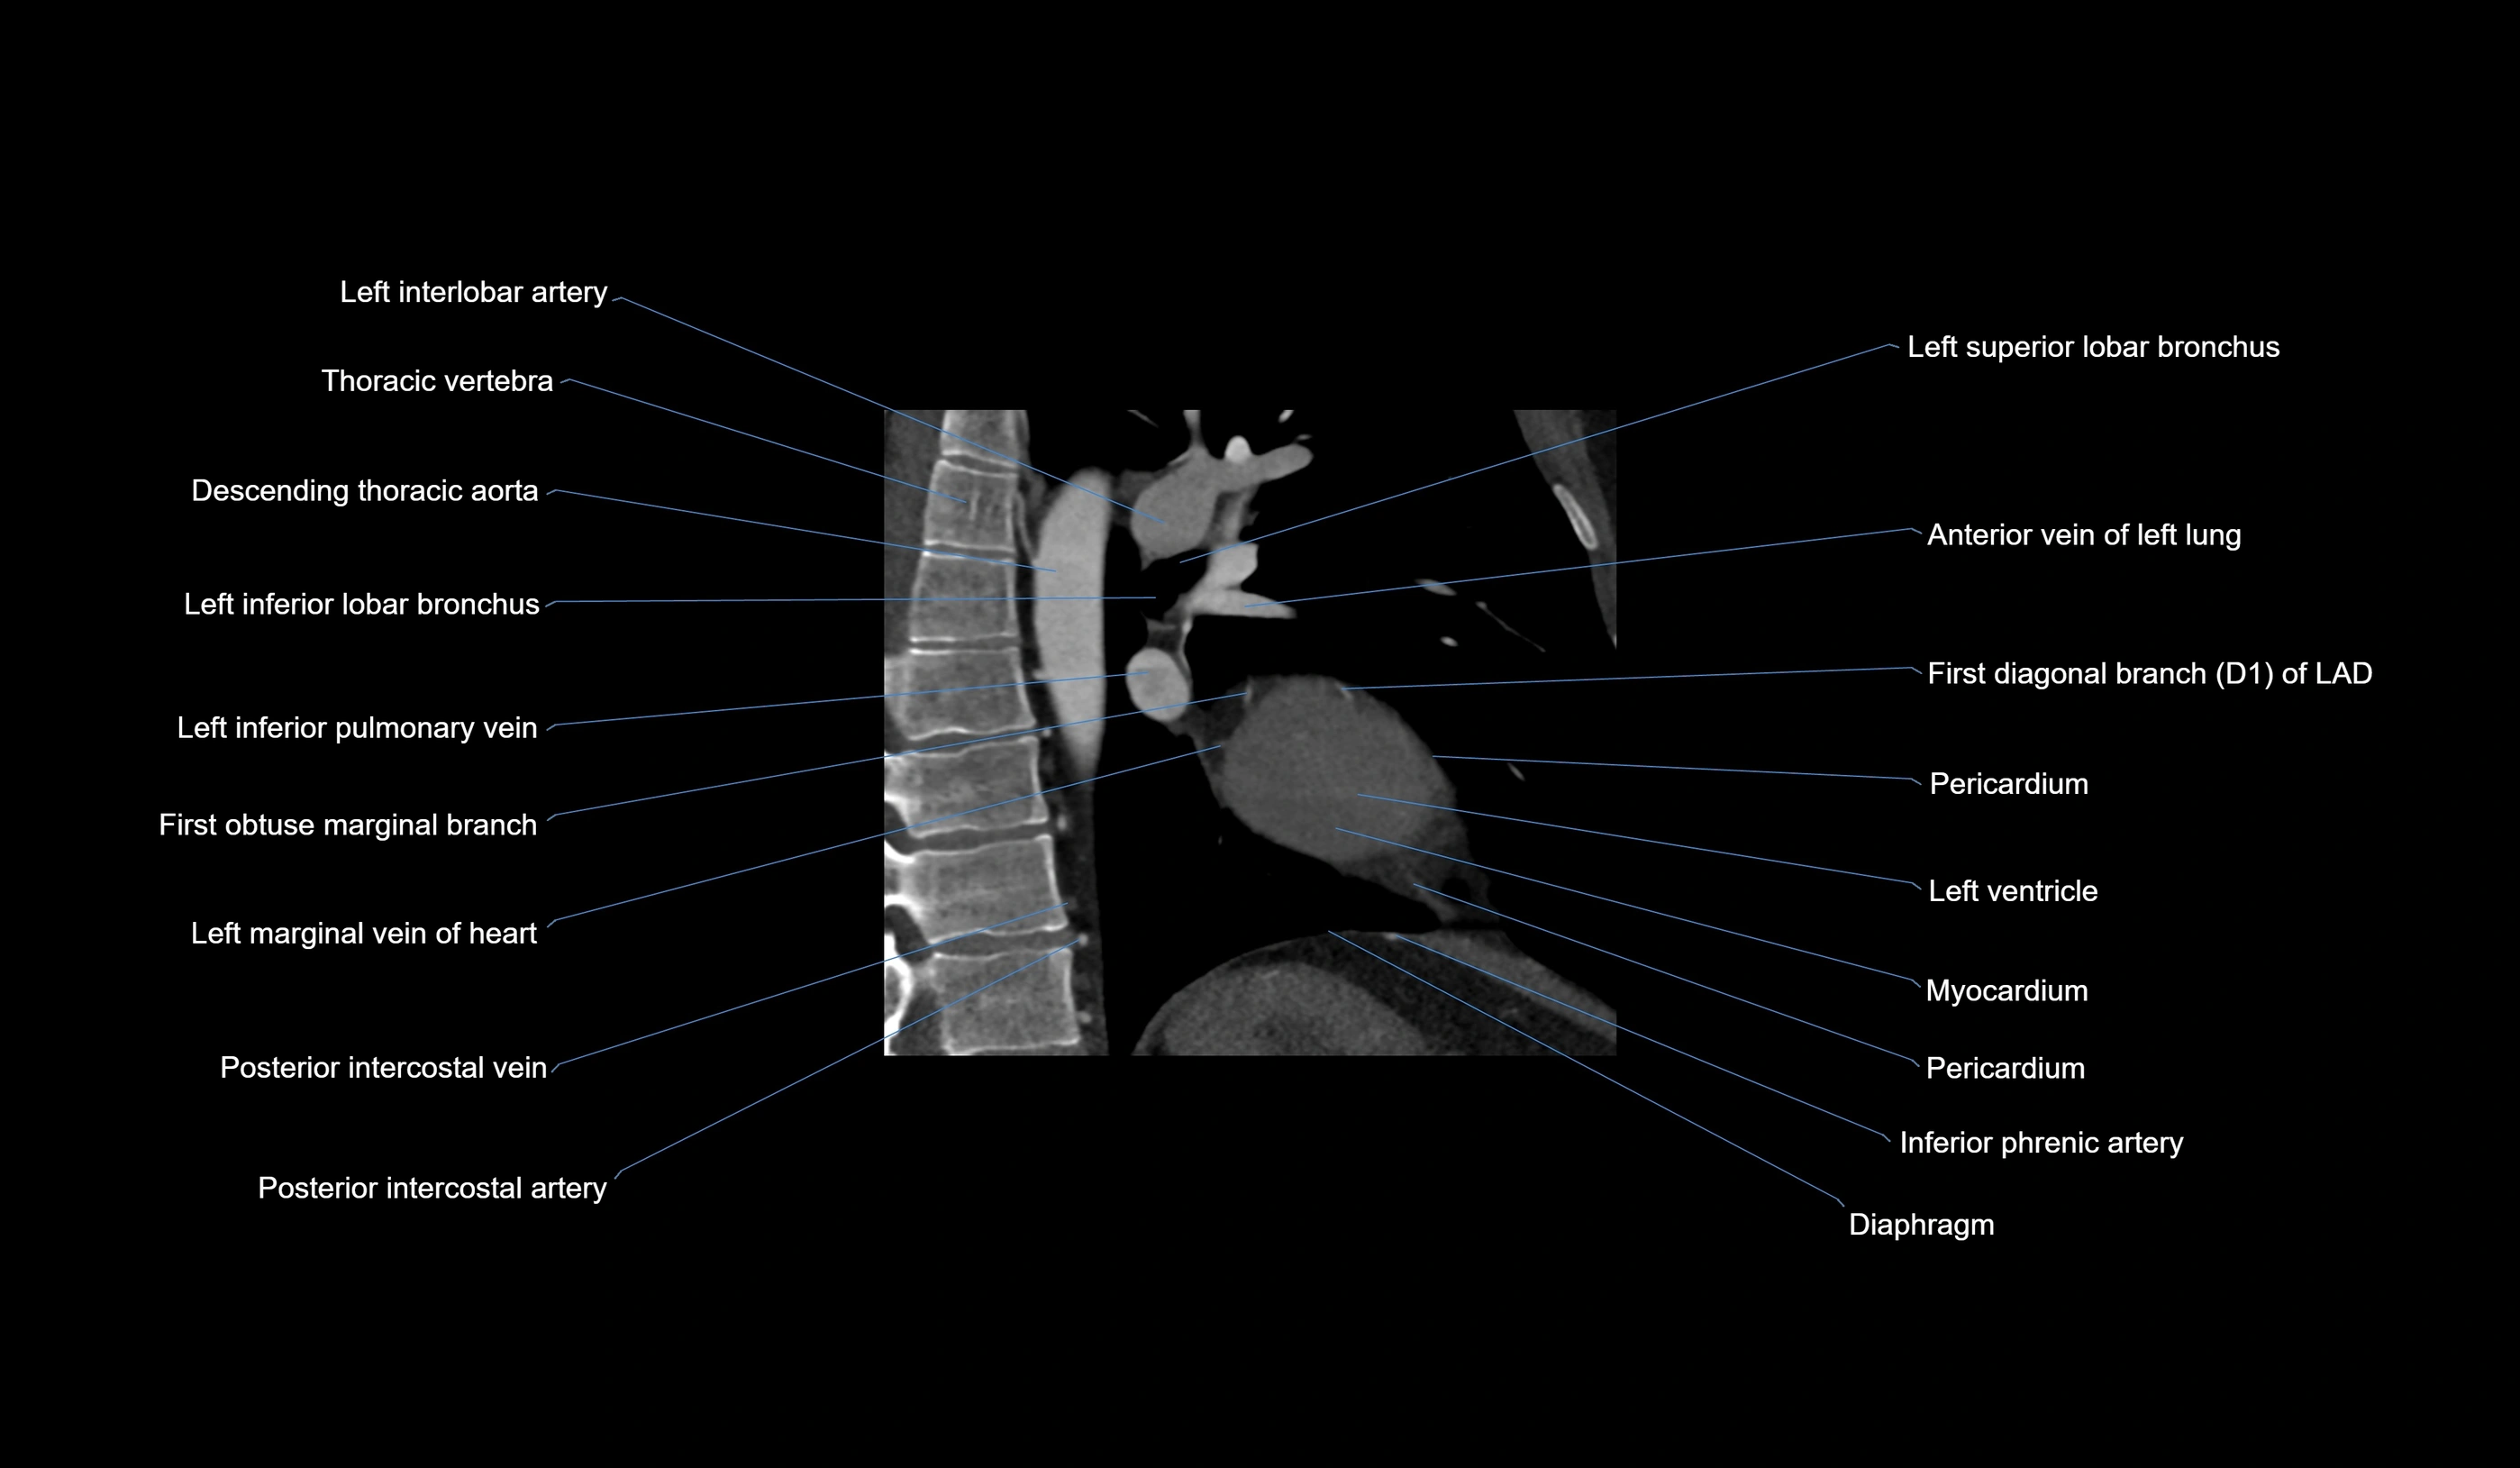

CT images